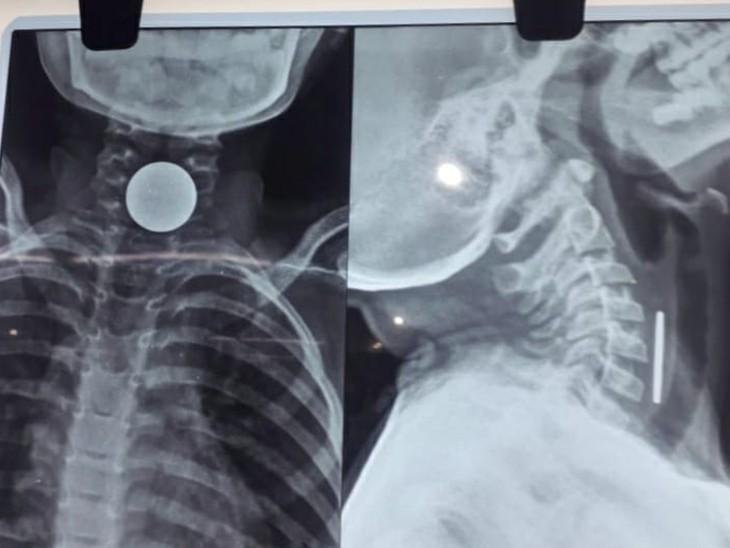

कोरबा (खबरगली) कोरबा जिले में एक 8 साल के मासूम बच्चे के सीने में सिक्का फंसने से उसकी मौत हो गई। शिवम सारथी ने सिक्का कब और कैसे निगला इसकी जानकारी परिजनों को भी नहीं थी। जब तबीयत बिगड़ी तब वे जिला अस्पताल लेकर पहुंचे। जहां एक्सरे रिपोर्ट में सिक्के फंसने की पुष्टि हुई। परिजनों का आरोप है कि कोरबा जिला अस्पताल के डॉक्टरों ने बच्चे की हालात गंभीर बताई और कहा कि इसकी दवा नहीं है यहां इलाज नहीं हो सकता कह दिया। जिसके बाद परिजन बच्चे को निजी अस्पताल ले जा रहे थे।

शुक्रवार (31 अक्टूबर) रात अचानक शिवम की तबीयत बिगड़ने लगी। उसके हाथ-पैर ठंडे पड़ने लगे और सांस लेने में दिक्कत होने लगी। परिजन उसे तत्काल जिला मेडिकल कॉलेज अस्पताल लेकर पहुंचे। डॉक्टरों ने जांच के बाद एक्सरे रिपोर्ट के आधार पर बताया कि शिवम के सीने में सिक्का फंसा है, जिससे उसे सांस लेने में परेशानी हो रही है। अस्पताल के डॉक्टरों ने कहा कि यहां इसका इलाज संभव नहीं है और बच्चे की हालत गंभीर है, इसलिए उसे किसी दूसरे अस्पताल ले जाया जाए। परिजन शिवम को एक निजी अस्पताल ले जाने की तैयारी कर रहे थे, लेकिन रास्ते में ही उसने दम तोड़ दिया।